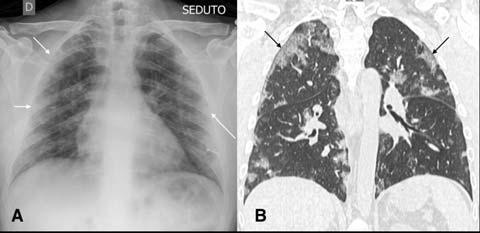

Imaging can play a vital role in assessing the severity of COVID-19 patients. To assess the extent of disease involvement, a simplistic radiographic scoring system was used by Wong et al12. Each lung was graded from 0-4 based on the extent of involvement (0- no involvement, 1- up to 25%, 2- 25-50%, 3- 50-75% and 4 >75% involvement). The scores of each lung were added to get a final score. The severity score of CXR varied over the time and peak severity was seen at 10-12 days from symptom onset (Fig 8). As the disease progresses the GGO are replaced by areas of consolidation that either resolves or worsens to give ARDS picture11 (Fig 9). Various CT severity scores have shown good correlation with clinical severity of disease20 21. The degree of lung inflation at the initial CT can also predict adverse outcomes in patients with COVID-1922

CXR for Disease progression/ Discharge decision :

Can CXR be used to decide when to discharge the

Fig 9 — Serial CXR examinations in a patient who succumbed to the infection. This patient came in with severe respiratory distress and was put on ventilator support early in his admission. ECMO therapy was also started (A) with bilateral parenchymal consolidation. Patient kept deteriorating on ECMO (Day 13- B, Day 18 C and Day 27- D) and succumbed to the disease. Images courtesy of Dr Amrita Bajaj, Glenfield Hospital, Leicester.

patient? No, there is no clear evidence to support this. In the study by Wong et al, there was no statistical difference between the time taken for radiographic and virologic recovery12. About 42% of patients had shown recovery in CT findings before RT-PCR test getting negative while the remainder either showed worsening of findings or showed improvement after RT-PCR became negative7

CXR resolution cannot be used to decide the time to discharge.